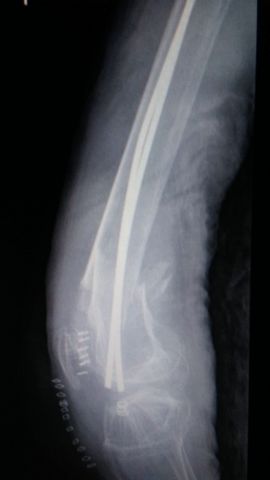

Fractura de diáfisis de húmero.

Fractura de húmero tras osteosíntesis con clavo gamma.